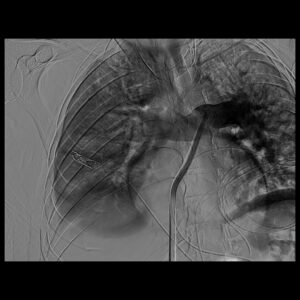

وكان المريض قد نُقل بشكل إسعافي من أحد المستشفيات وهو في حالة حرجة، نتيجة معاناته من ضيق شديد في التنفس وانخفاض حاد في مستوى الأكسجين، إثر انسداد كامل في الشريان الرئوي الرئيسي بسبب خثرات وريدية عميقة ظهرت بعد خضوعه لعملية منظار لمفصل الركبة.

وبفضل سرعة الاستجابة وجاهزية فريق الأشعة التداخلية جرى التدخل العلاجي العاجل وفتح الشريان الرئوي وسحب الجلطة بالكامل بدقة عالية، ما أدى إلى تحسّن فوري في العلامات الحيوية واستقرار الحالة دون تسجيل أي مضاعفات.